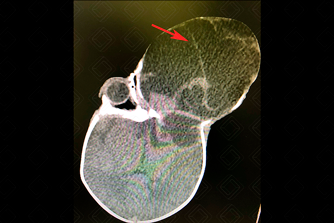

Texto alternativo para a imagem Figuras 1 e 2. Créditos: Dra. Elazir Mota - Rio de Janeiro/RJ

Descrição das figuras 1 e 2: Tomografia computadorizada da face, nos cortes coronal e axial, após a injeção no contraste. Paciente recém-nascido, 3 dias de vida, sexo masculino. Presença de volumosa lesão expansiva (seta vermelha), heterogênea, com componentes císticos e focos de calcificação no globo ocular esquerdo, com destruição do arcabouço ósseo e invadindo a fossa média craniana.

• Tomografia computadorizada da face: Em geral, como acometem comumente os recém-natos, o exame mais realizado para avaliação adequada da sua extensão, no período pós-natal, é a tomografia por tratar-se de exame que dispensa sedação. Nesse exame evidenciamos uma lesão heterogênea, com componentes císticos e focos de calcificação e impregnação após a administração do meio de contraste, alargando o arcabouço ósseo (figuras acima).